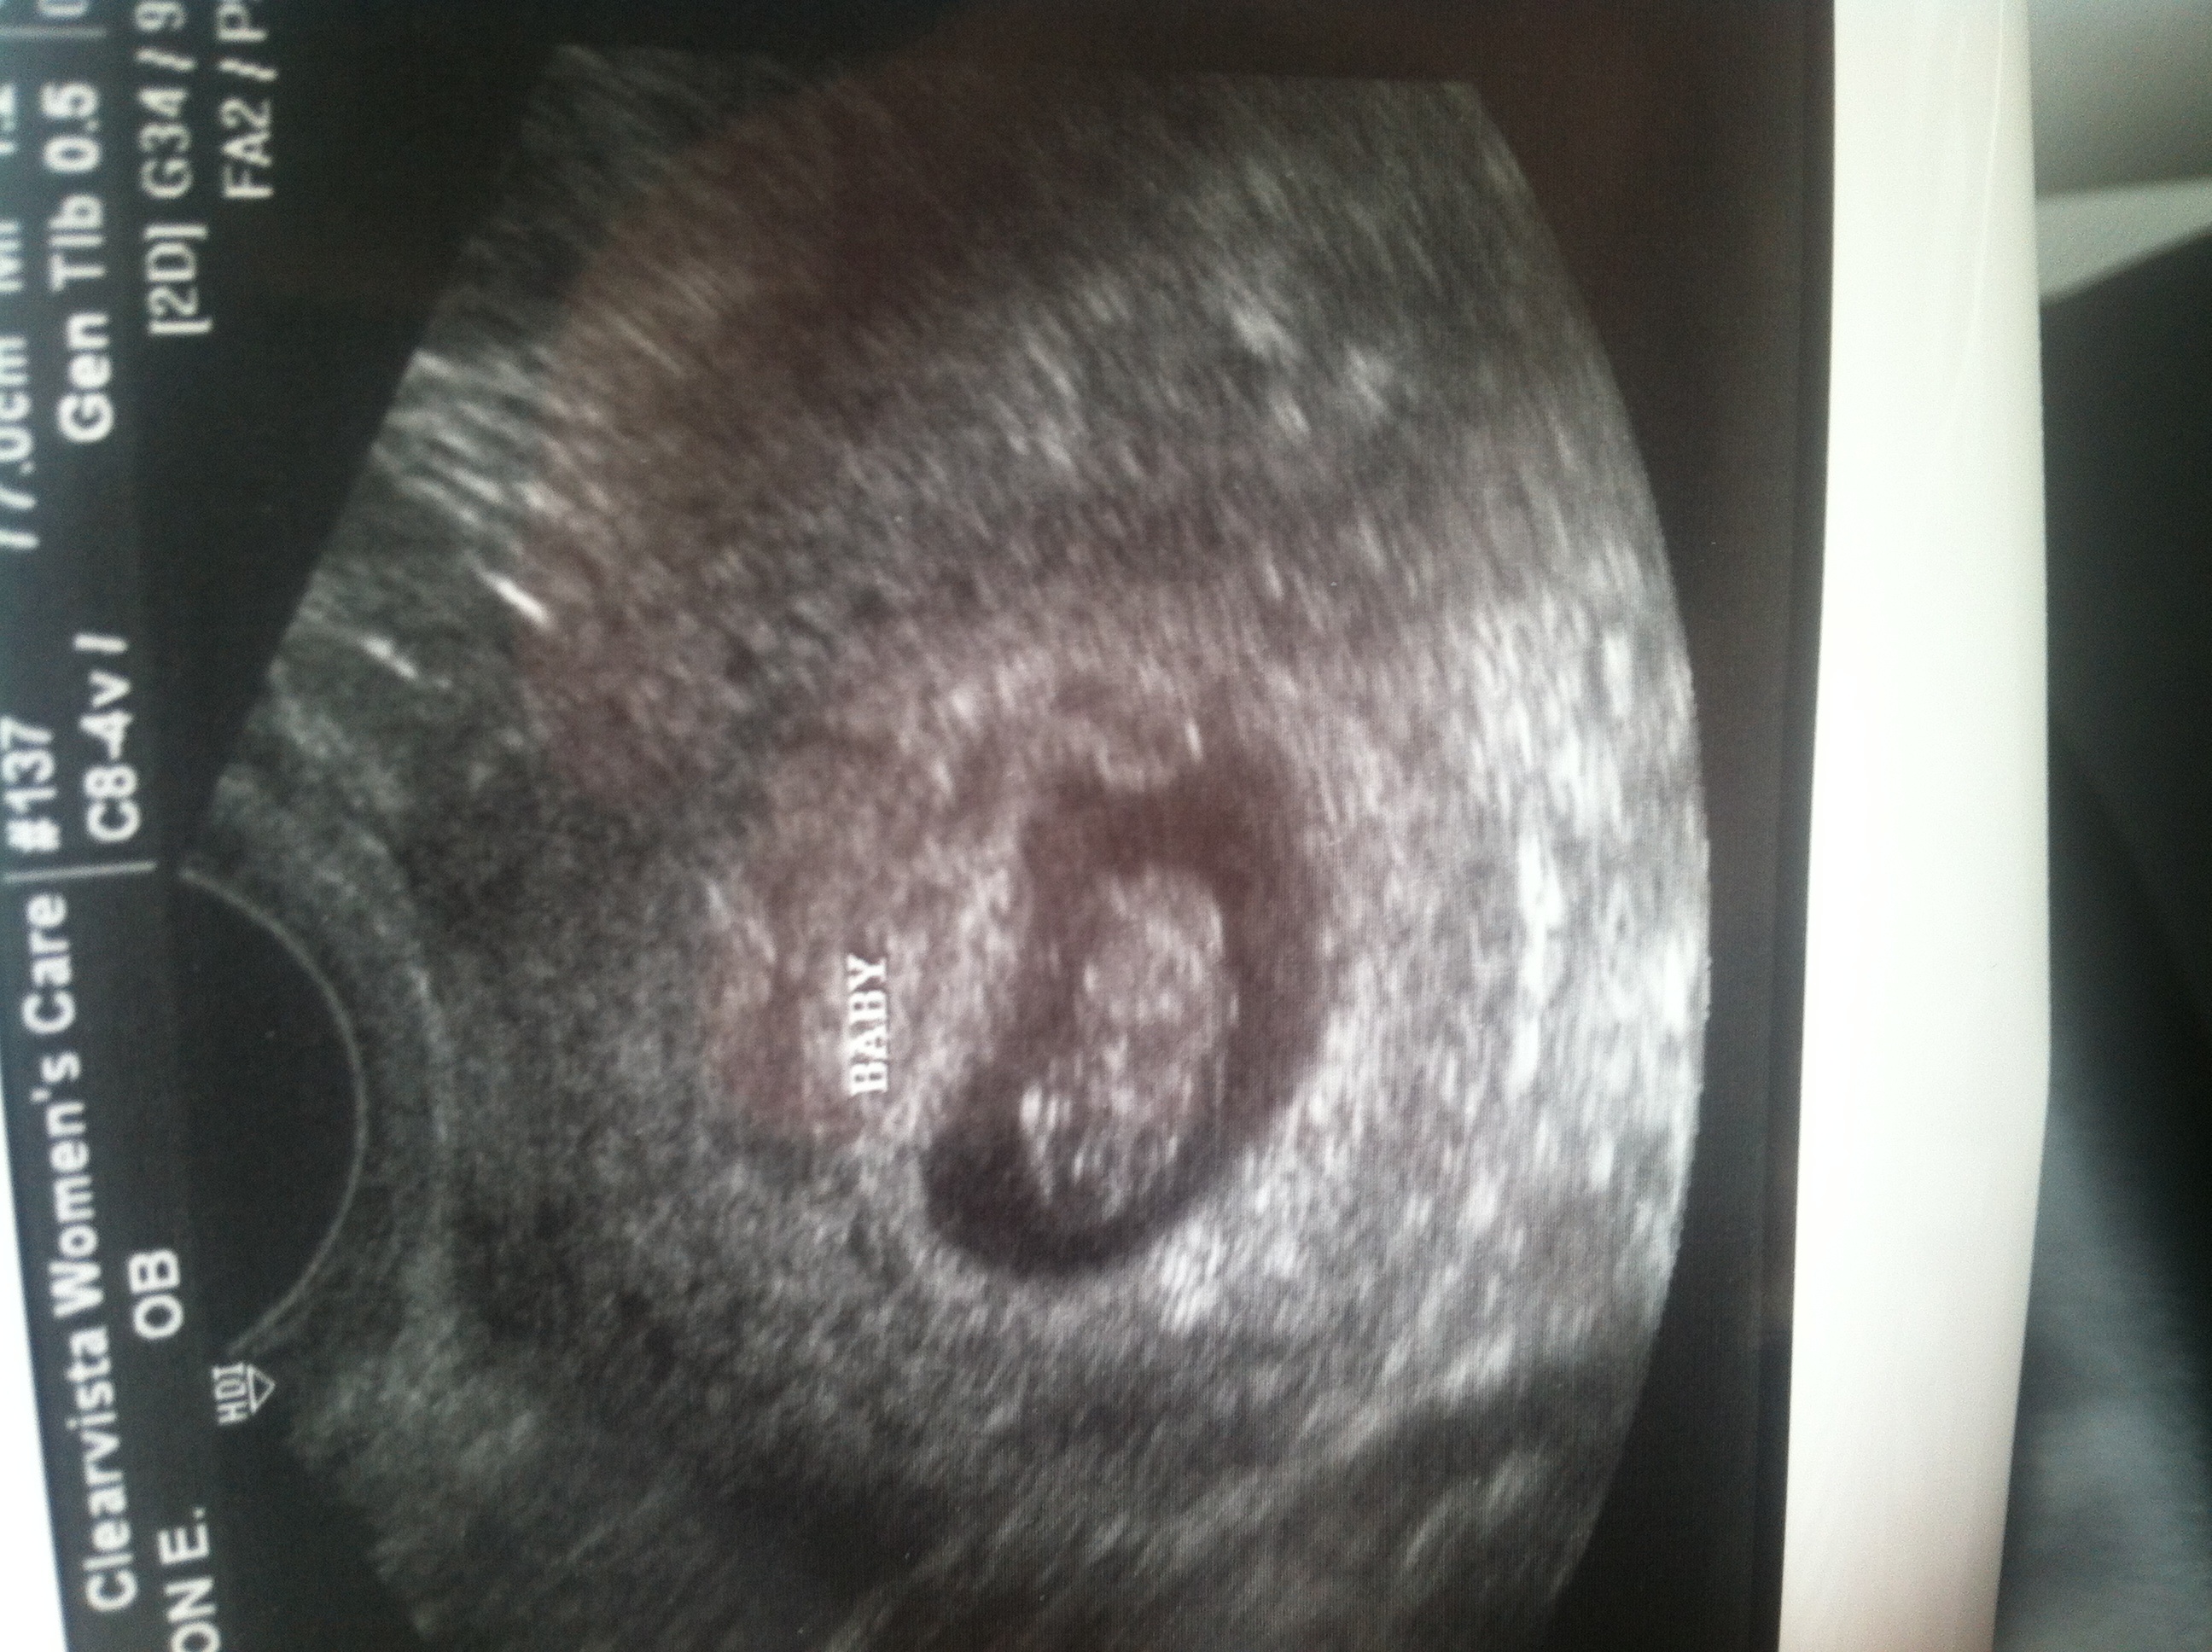

Baby was measuring 8w3d w/ a h/r of 183. So, one more hurdle cleared! I go back in 2 weeks.